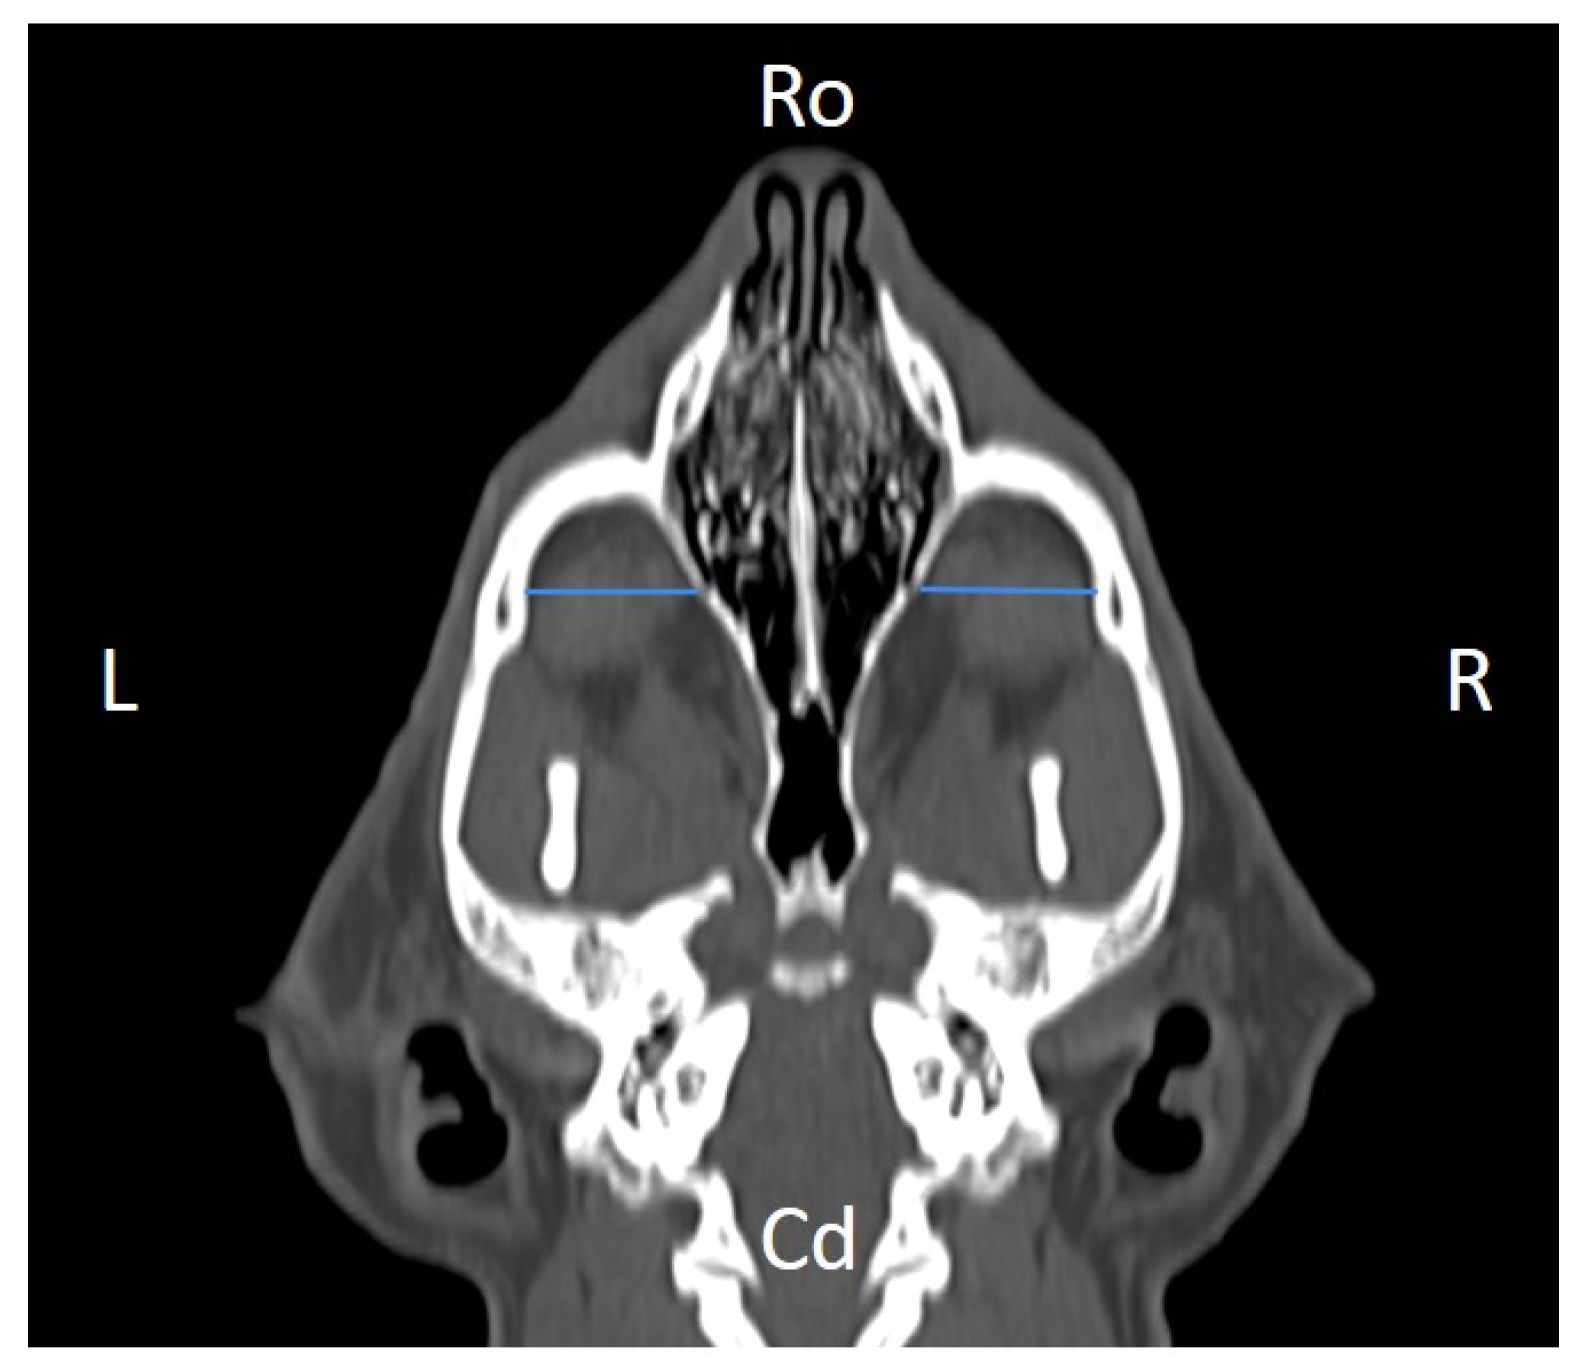

In order to perform the linear measurements described in Table 1, firstly, rotational misalignment of the head was corrected by aligning the images in the three planes, as demonstrated in Figure 1. The sagittal plane (Figure 1A) was aligned at the level of the nasal septum and the interincisive midline; the transverse plane (Figure 1B) was oriented perpendicular to the hard palate; and the dorsal plane (Figure 1C) was parallel to the hard palate. Since the computer program used allowed for the simultaneous visualization of the three anatomical planes (sagittal, transverse, and dorsal), the identification of the measurement planes and the delimitation of the anatomical structures to be measured was performed with greater precision.

Figure 1. Representative multiplanar computed tomography reconstruction showing the sagittal (A), transverse (B), and dorsal (C) planes. The sagittal plane was aligned at the level of the nasal septum and the interincisive midline; the transverse plane was oriented perpendicular to the hard palate; and the dorsal plane was parallel to the hard palate. D, dorsal, L, left, R, right, Ro, rostral, V, ventral.